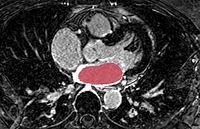

Gao Y., Gholami B., MacLeod R.S., Blauer J., Haddad W.M., Tannenbaum A.

Segmentation of the Endocardial Wall of the Left Atrium using Local Region-Based Active Contours and Statistical Shape Learning.

Proceedings of SPIE Medical Imaging 2010.